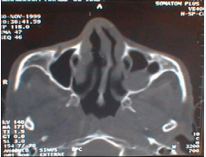

Figure 2 CT coronal plane: right maxillary mucocele (superior part of sinus).

Figure 2: CT coronal plane: right maxillary mucocele (superior part of sinus).

Symptomatology is not specific. We can found nasal obstruction, rhinorrhea, epistaxis, facial pain, facial deformation, proptosis, peri orbital swelling, epiphora, palatal deformity, dental problems or radiologic discovery. Nasal endoscopy shows anomalies of lateral nasal way (disformed). Computed tomography in the axial and coronal plane gives a reliable extension balance, the sinus is enlarged with wall blowed reduced or interrupted. Its contents isodense or hypodense and no contrast enhancement, unless infected.